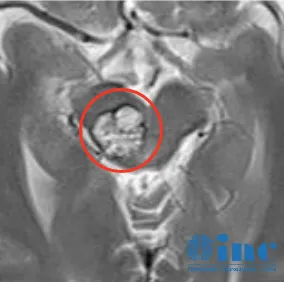

秦先生,一位脑干中脑海绵状血管瘤患者、脑干反复出血。

显微镜下,脑干海绵状血管瘤取出过程。